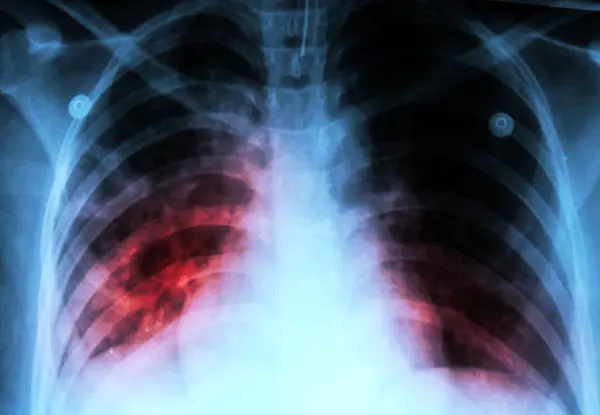

آمار وحشتناک دو بیماری هولناک در ایران

رکنا: آمار بیماری سل در ایران و ارتباط آن با ایدز توسط محققان کشوری سنجیده شد.

دکتر پیام طبرسی همزمان با هفته اطلاع رسانی ایدز HIV با اشاره به آمار سل در ایران و ارتباط آن با بیماری HIV، گفت: آمار سل در ایران بر اساس تخمین سازمان جهانی بهداشت، ۱۴ در ۱۰۰ هزار نفر است که حدود ۸۰ درصد موارد شناسایی میشوند و با اینکه در حال حاضر وضعیت کشور ما نسبت به منطقه مطلوبتر است با این حال جای کار بیشتری وجود دارد.

وی با بیان اینکه حدود ۳.۸ درصد بیماران دارای سل، به HIV نیز مبتلا هستند، گفت: این مساله درمان افراد را با مشکل روبرو کرده که به همین دلیل نیازمند مراقب بیشتر برای آینده هستیم.

معاون آموزشی بیمارستان مسیح دانشوری در ادامه با اشاره به برخی راههای تشخیص بیمار مسلول، اظهار کرد: بیماران مسلول افرادی هستند با علائم سرفه بیش از ۲ هفته خلط خونی، تعریق شبانه، کاهش وزن، تب طولانی و غیره که باید حتما بررسی شوند. راه عمده شناسایی سل ریوی انجام آزمون اسمیر و کشت خلط از نظر میکروب بیماری سل است و این آزمایش در اکثر آزمایشگاهها و مراکز بهداشتی انجام میشود.